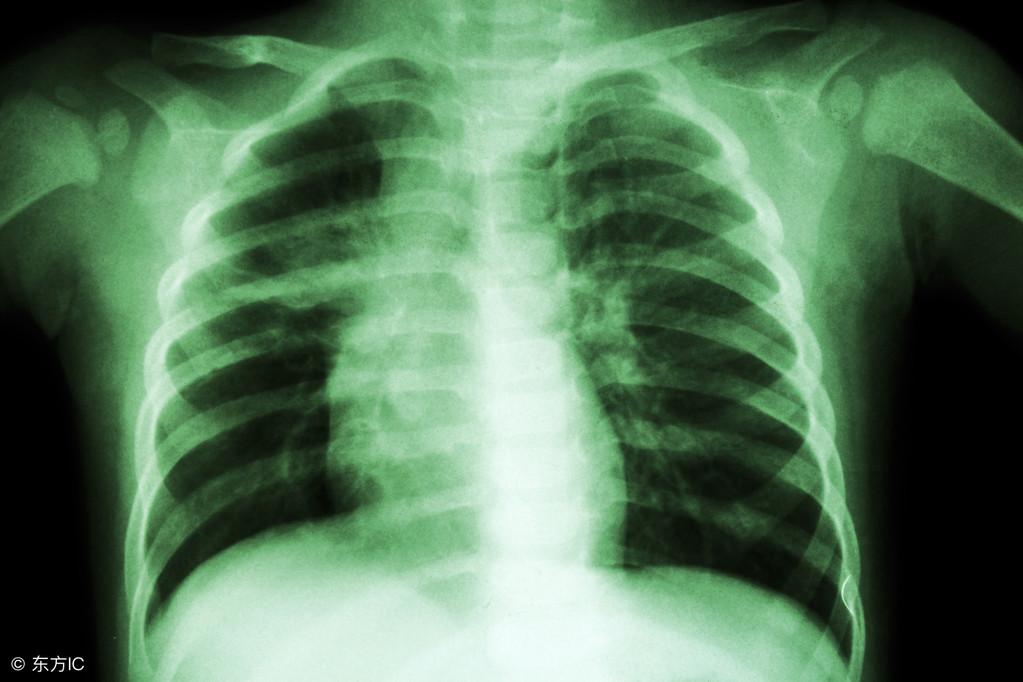

矽肺,是一种因长期吸入矽尘而引发的肺部疾病,给患者带来极大的痛苦,随着医学的不断发展,我们有了对抗这一疾病的全新武器——最新研发的矽肺药物,它的研发历程就像一场漫长的马拉松,凝聚了无数研究者的汗水、坚持与智慧。